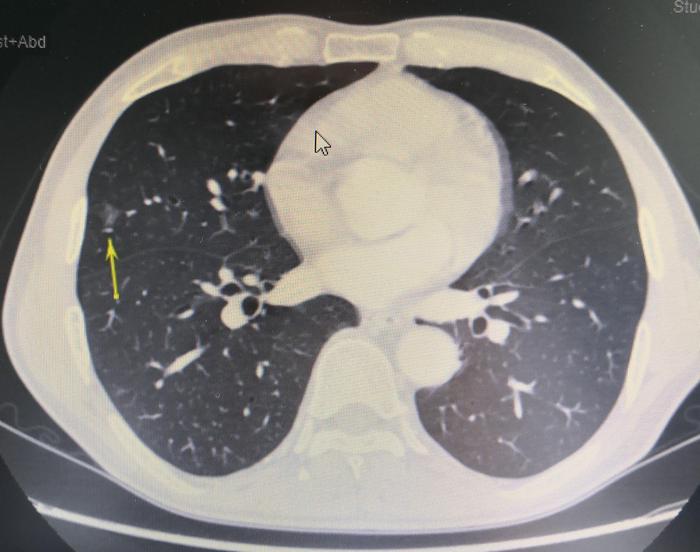

病人的中肺磨玻璃结节大约9×10毫米大小。在我院复查CT长下面这个样子。

上图(图1),黄色箭头指示的是右中肺磨玻璃结节。